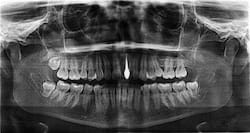

Have Bleeding Gums and Pus? Dentists Warn It Could Be a Sign of Periodontitis

Bleeding gums or pus near your teeth may be early signs of periodontitis. Learn the symptoms, risks, diagnosis steps, and expert advice to protect your teeth and overall oral health.